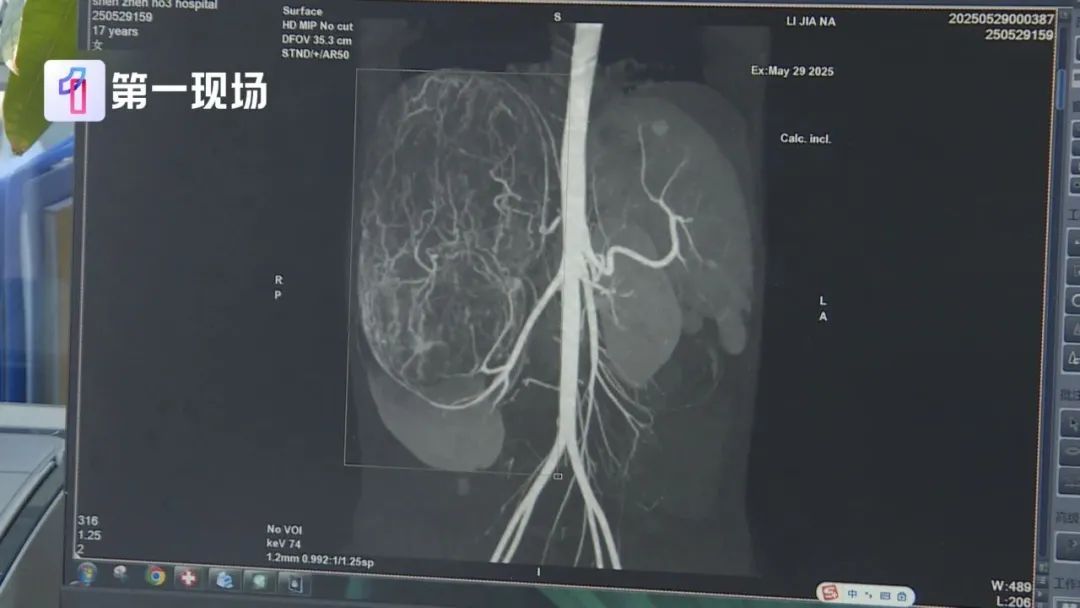

到了医院一检查,CT结果显示,婷婷的右肾有恶性肿瘤伴肝转移可能,家长立即带着孩子来到深圳求医。

送医后,医生表示,肿瘤体积过大,几乎占据了整个腹腔,周边器官也被严重挤压。经过多轮讨论,最终医生决定创新尝试国外的“反L型”切口开腹策略。

肿瘤切出来后,医生测量大小发现直径达27厘米,重量有2.435公斤,非常非常的大。